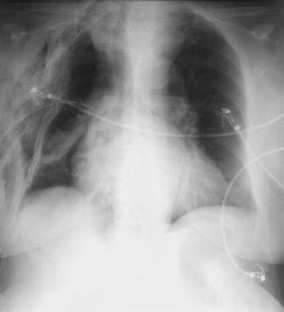

Abb. 1

Abb. 2a, b